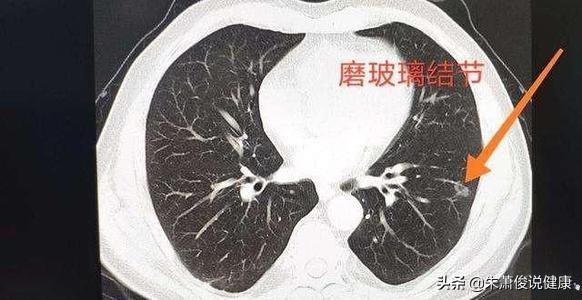

Knötchen werden in feste und gemahlene Glasknötchen unterteilt

Lungenknoten werden je nach ihrer Dichte in verschiedene Typen eingeteilt: Knoten mit höherer Dichte, die auf dem CT der Brust als weiße Punkte erscheinen, werden als solide Knoten bezeichnet, während Schliffknoten eine geringere Dichte haben und wie Wasserdampf auf dem Glas aussehen. Glasschliffknötchen, insbesondere reine Glasschliffknötchen, sind in der Regel bösartiger.

1. feste Knötchen2.Partieller fester KnotenGemischte gemahlene Glasdichteknollen; 3.nicht fester Knötchen: Vollständig gemahlene Glasknollen.

Die Dichte dieser drei verschiedenen Arten von Lungenknoten in der CT-Bildgebung ist von großem klinischen Wert für die Bestimmung des gutartigen oder bösartigen Charakters von Lungenknoten in Kombination mit anderen Zeichen.